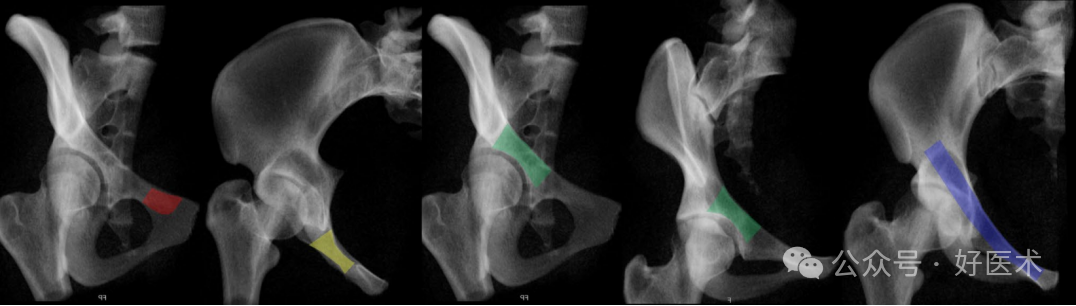

在放射影像上,若能够识别髂后皮质骨(骨盆边缘)、髋臼上软骨下骨(髋臼顶)、耻骨中部下骨皮质以及增厚的弯曲的皮质表面,则视为**观察视角。Eastman等人推荐了骨盆入口位(Pelvic Inlet View, PIV)和联合闭孔出口位(Combined Obturator Oblique Outlet View, COOO)。由于个体差异和性别解剖学的不同,没有报告关于影像增强器定位的标准值。此外,不推荐完全重叠的上下耻骨支(通过骨盆超入口位,Pelvic Hyper-Inlet View, PhIV)的影像。使用PIV时,可以看到后上方的耻骨支表面位于后下方耻骨支表面的后方(表现为一个小的闭孔阴影)。这种视角下,耻骨支的中部区域显示不充分。COOO视角是**的,如果它显示了中支区域的**宽度,这需要对图像增强器进行一些微调。Rommens等人还推荐了PAP视角。PIV视角是从“上方”观察,而COOO视角是从侧方观察。推荐的X光摄片顺序包括(图14):

图14 逆行上支螺钉或顺行前柱螺钉的放射影像序列:COOO、高入口位、COOO、COOI和骨盆入口视图,各视图均对应**导针分布区域(彩色显示)。

-COOO:用于确定靠近耻骨结节的进钉点。

-使用PIV视图监视:直至钻头尖端接近(经典的)骨折线。

-COOO:用于确认钻头在关节周围的导向(额外的COOI视角有助于提供第二个平面)。

-PIV:用于显示整个上支内的完整路径。